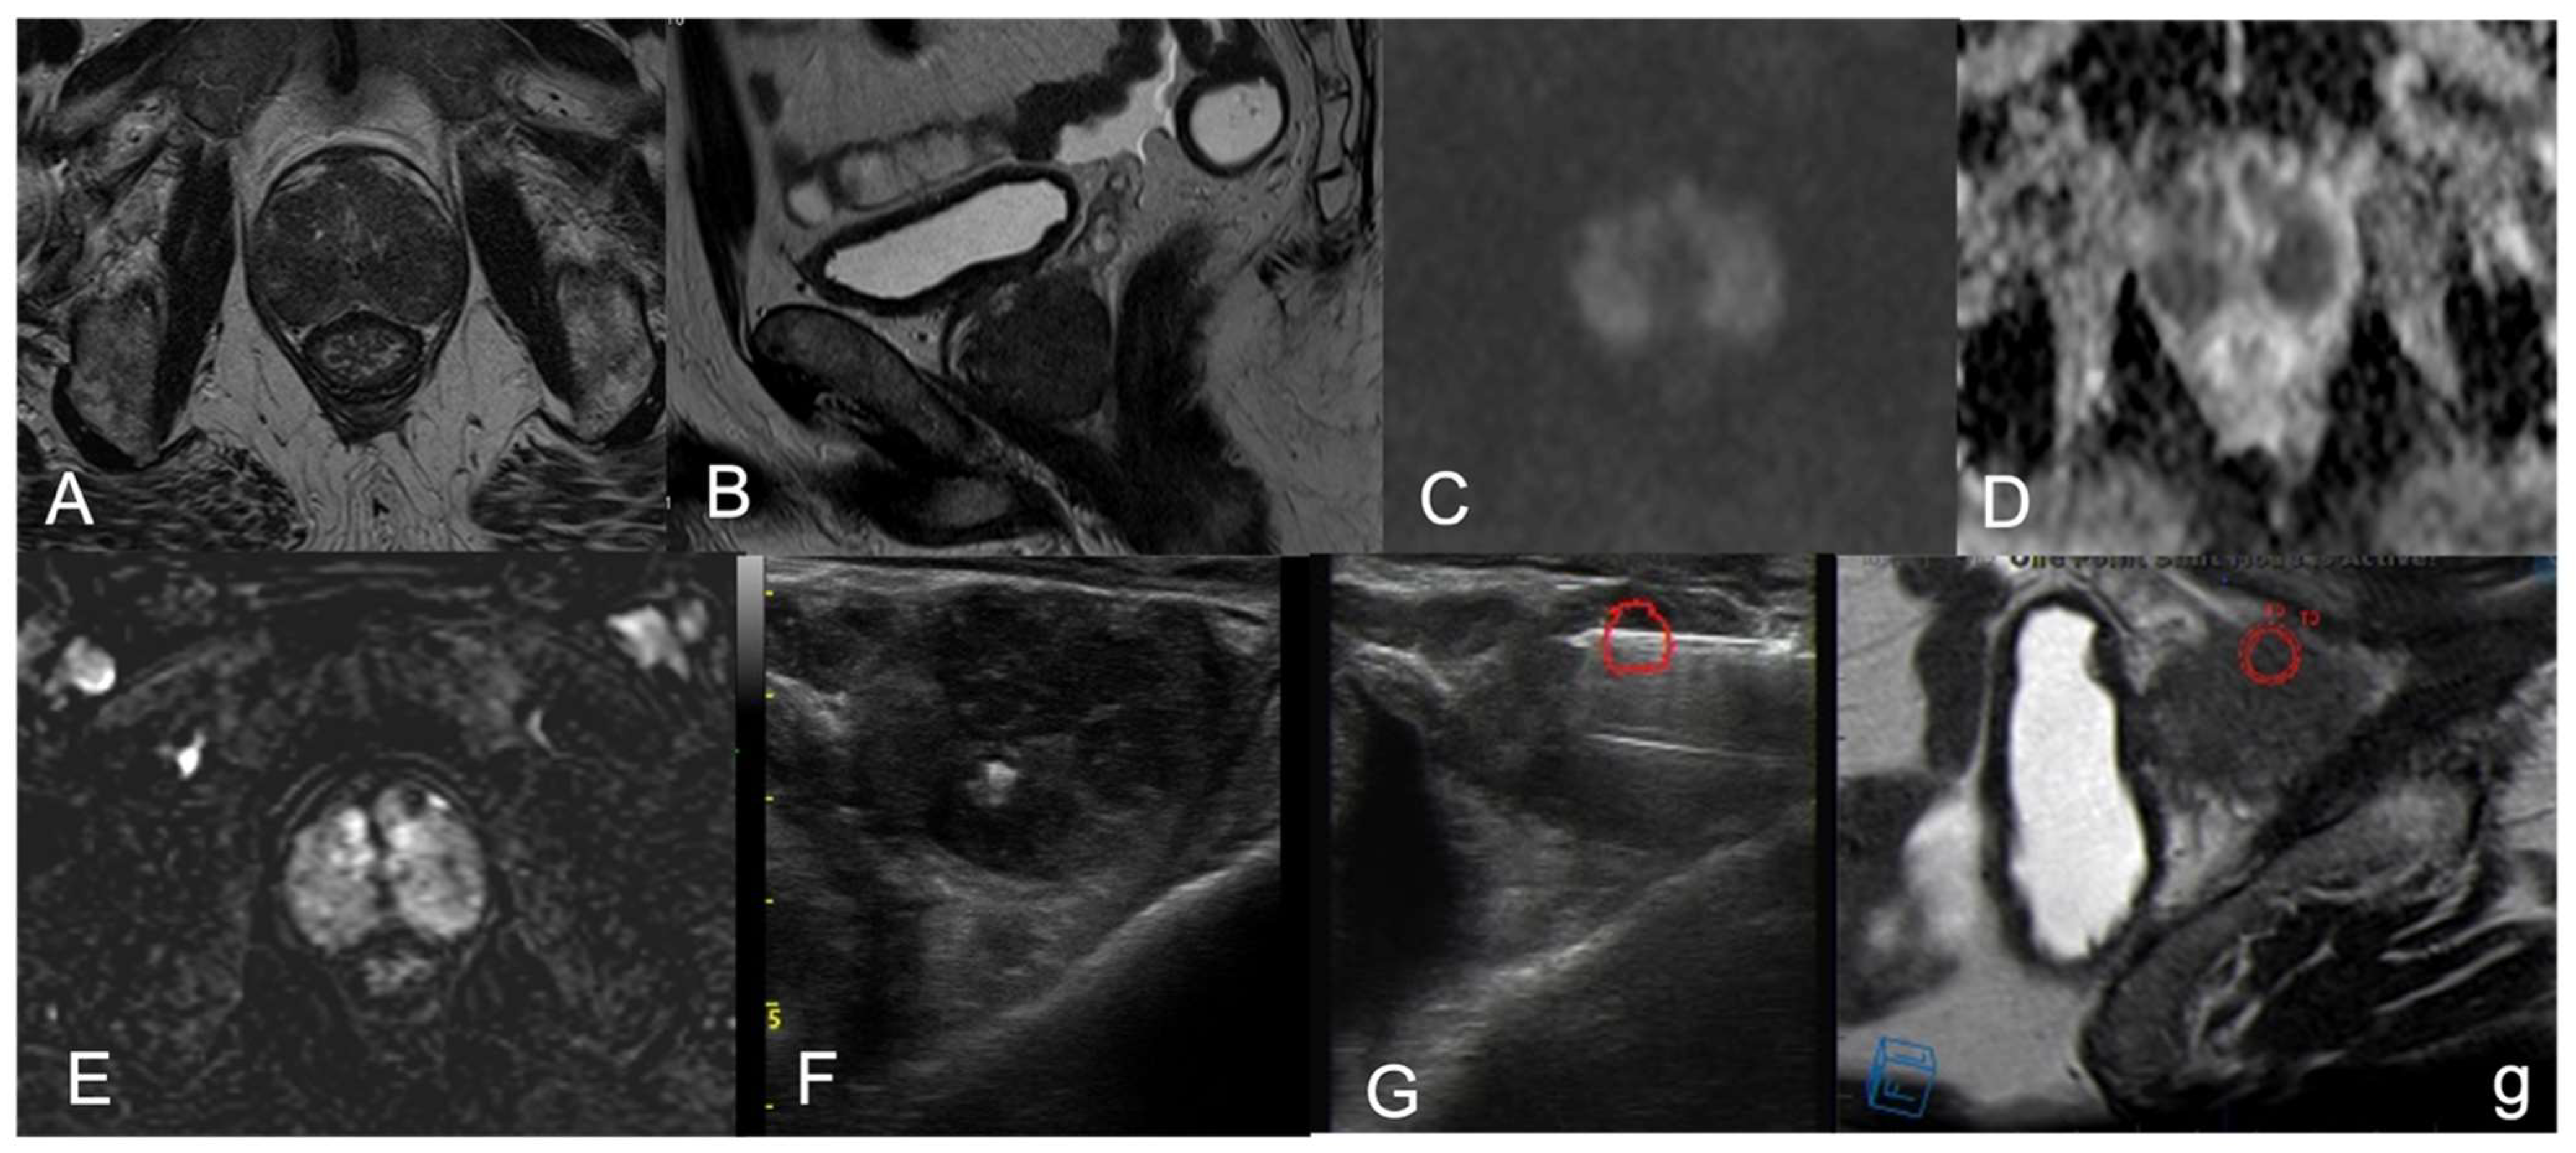

| 1 | PZpm mid-left; TZa mid-base right | 2-cm hypointense PZ nodule; 1.5-cm marker hypointense irregular TZ lesion | Isointense nodule; Slightly hyperintense | Marked low ADC value; Low ADC value | Peripheral rim enhancement and avascular core; Inhomogeneous, early and prolonged hyperenhancement | 4; 5 |

| 2 | PZpl mid-left | 2.5-cm hypointense nodule, capsular bulging | Hyperintense | Low ADC value | Thick peripheral rim enhancement, avascular core | 4 |